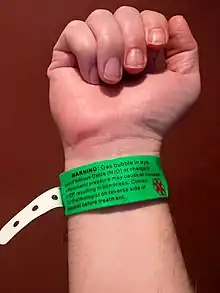

A gas bubble may be placed inside the eye, to keep the retina in place. If a gas bubble is used, sometimes a certain head positioning (posturing) has to be maintained, such as face down or sleeping on the right or left side. The gas bubble will dissolve over time, but this takes several weeks. Flying should be avoided while the gas bubble is still present.